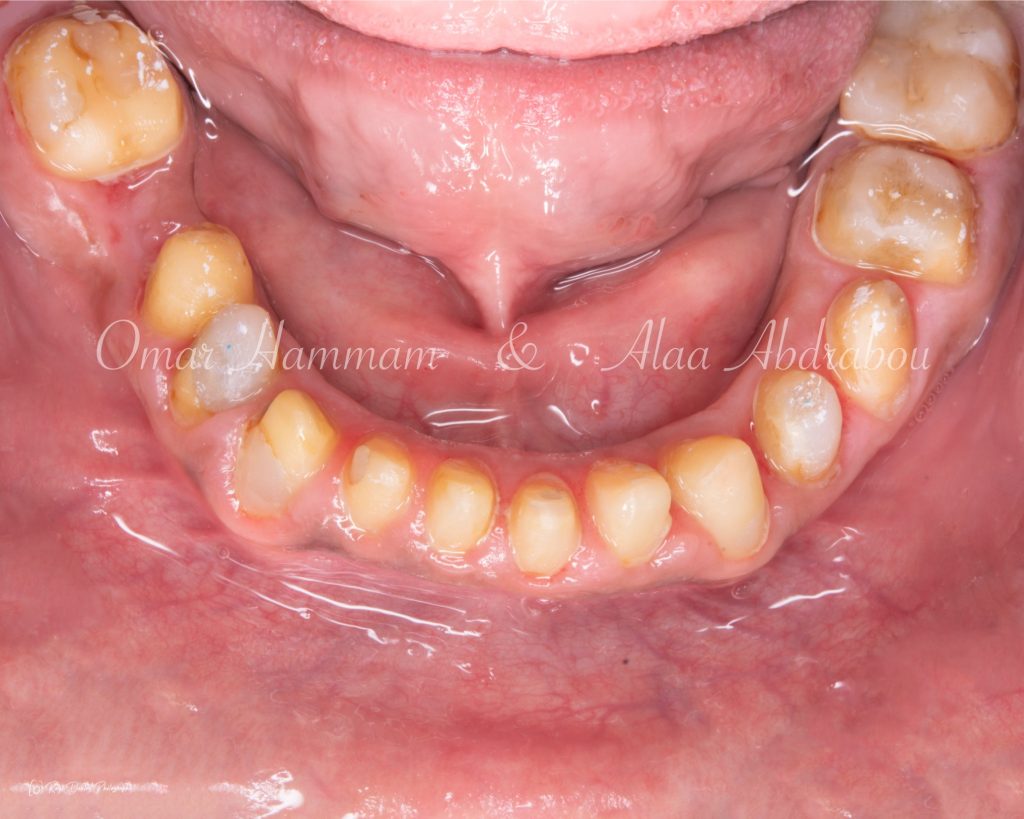

The optimum occlusion tried to be established at the right side to be half unit "Cusp to Cusp" occlusion, as the patient suffers from two different occlusion classes on the both sides and on the same side between the molar and canine relationships, to distribute forces more evenly across the occlusal surfaces promoting stability and longevity of the restoration.

Immediate occlusal scheme after cementation (before any adjustments):

Showing “Occlusal equilibration”, where Stable occlusion is achieved , in which there are Stable contacts of equal intensities on all teeth in centric occlusion showing Group Function occlusion.

Occlusal forces are distributed on more occlusal contacts, Acting as a group to distribute occlusal forces, thereby increasing efficiency of mastication and performing lateral movements atraumatically.